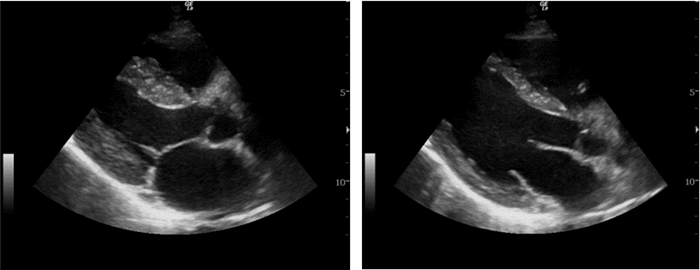

①视觉评估:胸骨旁左室短轴切面下,左室应呈同心圆样运动,左室内径变化率及室壁增厚率均大于50%,甚至出现收缩期心腔排空现象,提示左室高动力改变(图 3);左室内径变化率10%~25%、室壁增厚率30%~50%,提示左室收缩功能中度减低;心室内径变化率小于10%、室壁增厚率小于30%,提示左室收缩功能严重减低(图 4)。②胸骨旁左室长轴切面二尖瓣尖水平M型检查:a.测定二尖瓣尖与室间隔间最小距离(EPSS,e-point septal separation),正常值≤5 cm,合并主动脉瓣返流、二尖瓣狭窄、基底部室间隔增厚时此法存在误差。b.测定左室短轴缩短率=(左室舒张末内径-左室收缩末内径)/左室舒张末内径,正常值25%~45%,此法不适用于存在心尖和/或基底部室壁运动障碍患者。③于心尖四腔切面描迹收缩及舒张末期左室心内膜轮廓,利用辛普森方程测定左室射血分数,LVEF<50%,提示左室收缩功能减低。

| 图 3 左心室高动力改变(左图为收缩期,右图为舒张期) |